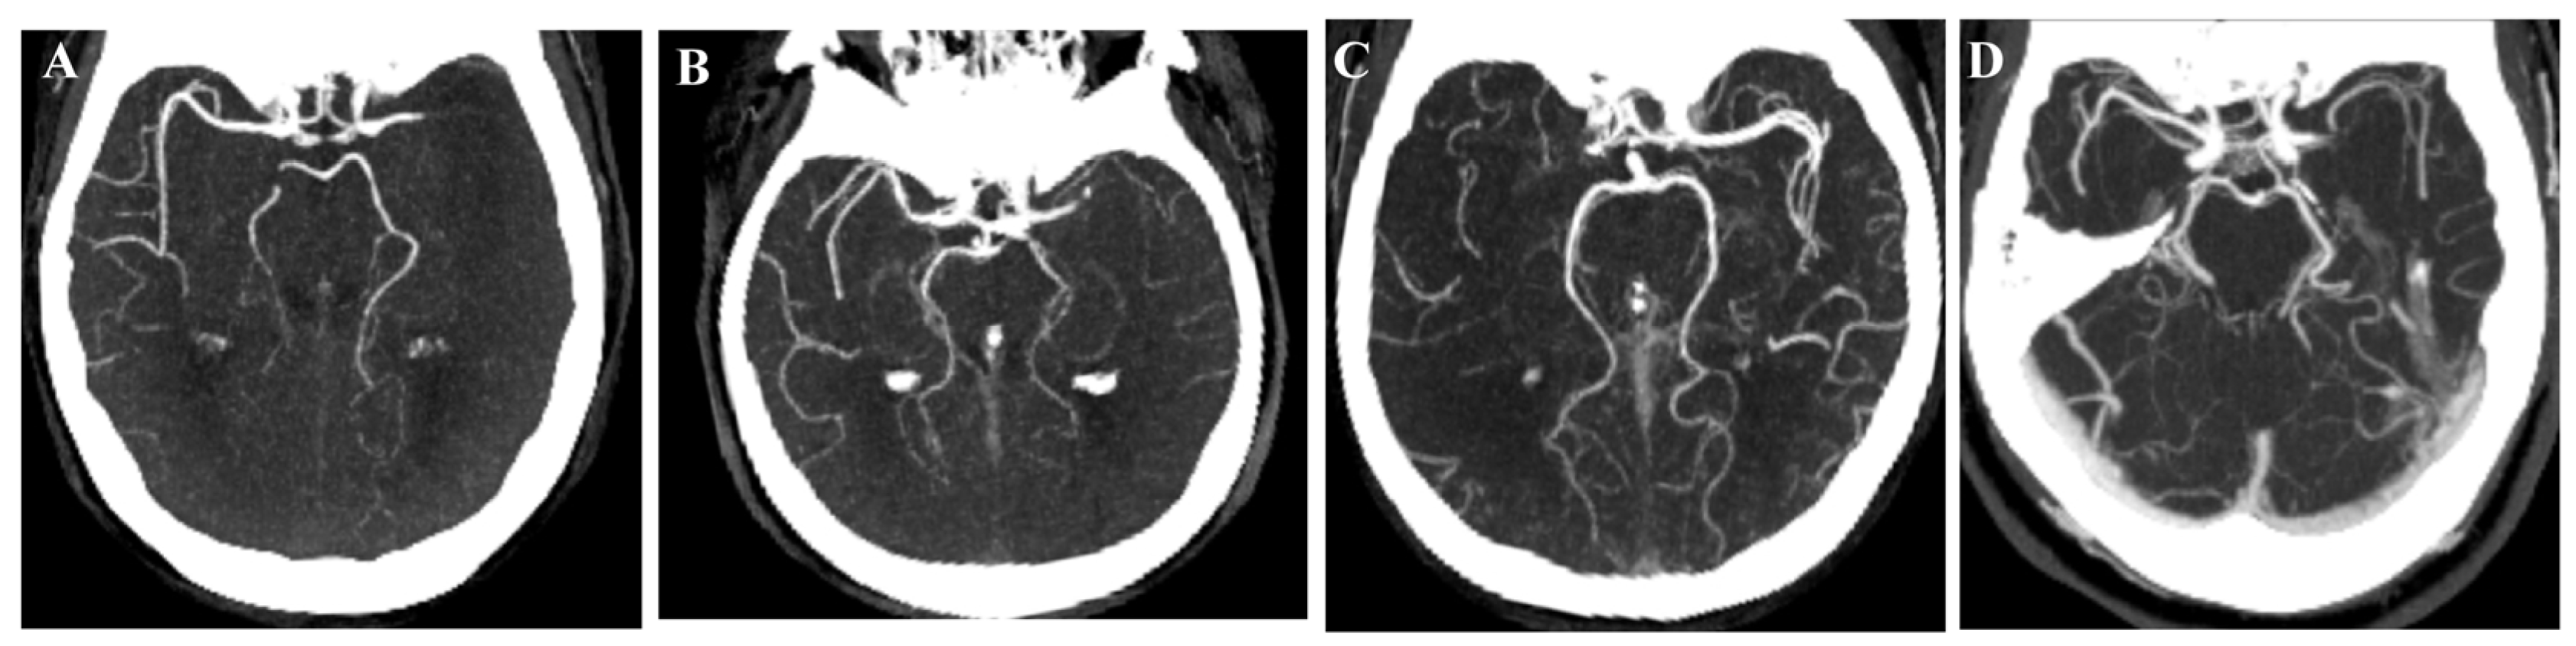

- Santos, T.; Carvalho, A.; Cunha, A.A.; Rodrigues, M.; Gregório, T.; Paredes, L.; Costa, H.; Roriz, J.M.; Pinho, J.; Veloso, M.; et al. NCCT and CTA-based imaging protocol for endovascular treatment selection in late presenting or wake-up strokes. J. Neurointerv. Surg. 2019, 11, 200–203. [Google Scholar] [CrossRef]